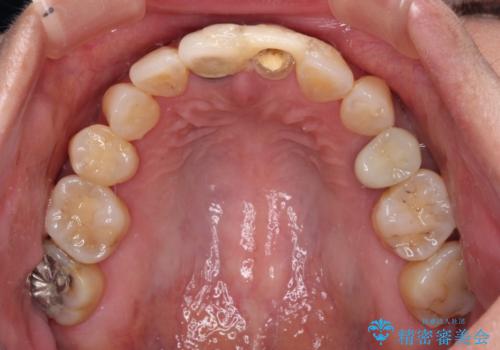

- 治療中の前歯の仮歯がひどい状態であるとのことで来院された患者様です。

治療中の前歯は根管治療の途中であり、根尖部に痛みを感じる状態でした。

まずは審美的な仮歯を装着し、根管治療を行った後にオールセラミッククラウンにて補綴治療を行うこととしました。